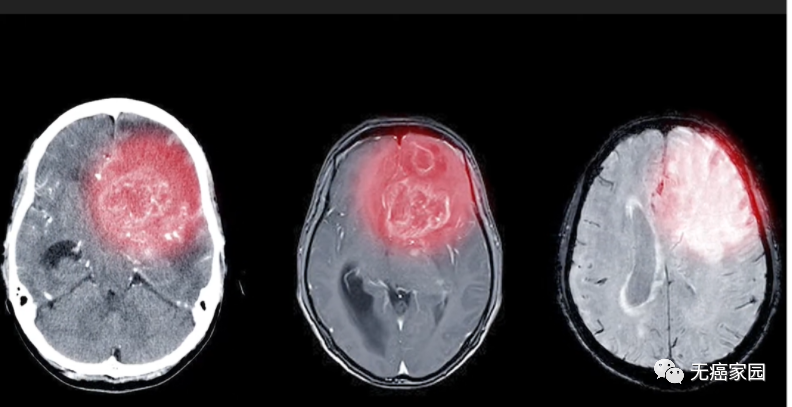

目前,NeoVax治疗脑瘤、肾癌、黑色素瘤的临床试验正在积极开展中。其中一项Ⅰb期的试验数据显示,NeoVax治疗脑胶质瘤中恶性程度最高的胶质母细胞瘤,中位无进展生存期PFS达到16.8个月。期待这些临床试验能带来积极的结果,并早日造福人类。